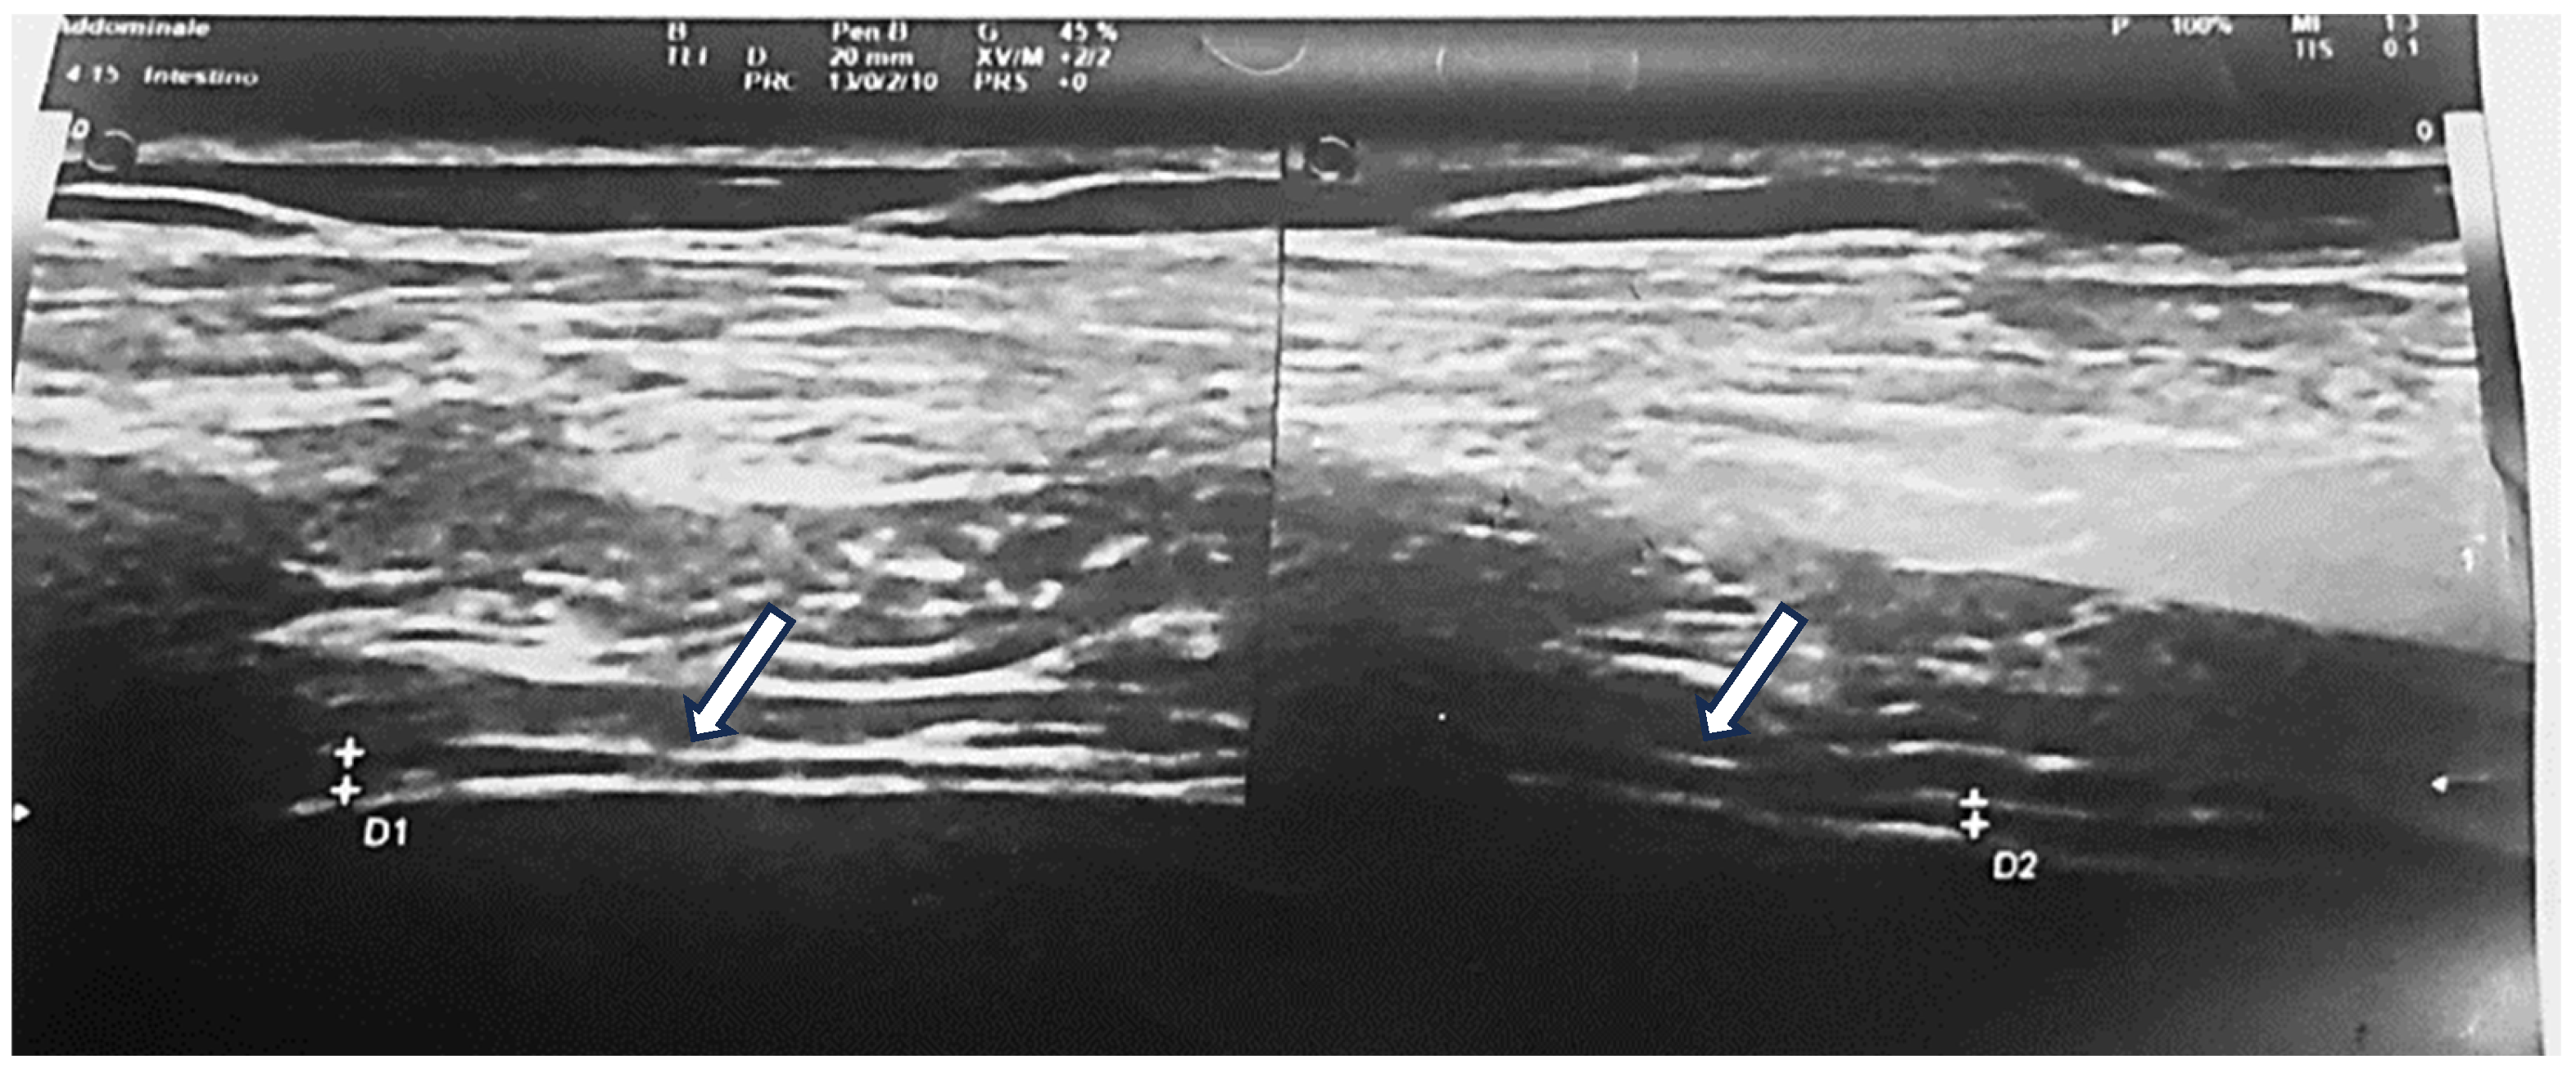

Diaphragm (DM): The diaphragm was assessed at the right mid-axillary line, at the 8th or 9th intercostal space, in a 30° head-up supine position. Measurements were obtained perpendicular to the diaphragmatic plane to assess muscle thickness at both end-expiration and maximal inspiration. Additional measurements were taken in the apposition zone (between lung and liver on the right, and lung and spleen on the left) in the 9th–11th intercostal spaces, 0.5–2 cm above the costophrenic angle. Diaphragmatic expansion was calculated, and a diaphragm-to-height ratio (mm/m) was derived (Figure 2).

Figure 2. Diaphragm was evaluated at the mid-axillary line on the right side, at the level of either the 8th or the 9th intercostal space depending upon the clearest image, in a 30° head up supine position, the probe held perpendicular to the diaphragm, for muscle thickness.